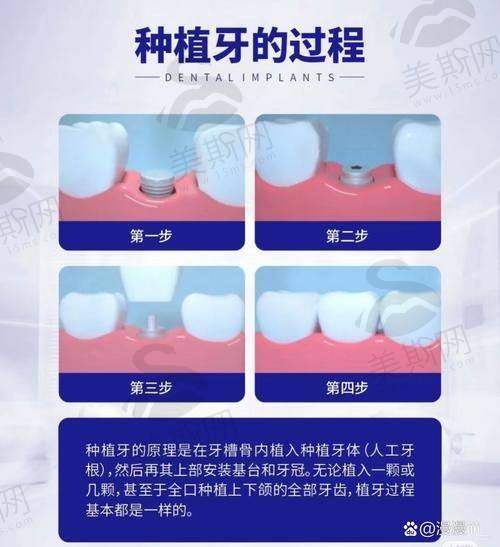

1. 数字化微创种植技术:采用3D导航精细种植系统,通过术前数字化扫描和模拟设计,实现种植体的精细植入,手术创伤小、修复快,适用于单颗、多颗及全口牙缺失患者。

数字化微创种植技术是医院的核心竞争力之一,该技术通过口腔CT三维扫描和计算机辅助设计,精细获取患者牙槽骨数据,在术前即可模拟种植体的植入位置、角度和深度,制定个性化种植方案。手术过程中,医生借助3D打印导板进行精细引导,避免了传统种植手术中对牙槽骨的过度损伤,手术时间缩短30%以上,术后肿胀和疼痛反应轻微,患者当天即可进食。该技术适用于各种复杂牙槽骨条件,即使是骨量不足的患者,也可通过即刻种植、骨增量等技术实现理想的种植成效,种植体存活率高达98%以上。

1. 广东广州柏德口腔(海珠院区)数字化微创种植牙:8000 - 15000元/颗